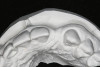

Figure 13   Exploiting study casts for planning single-tooth implant placement and restoration: Mounted study casts permit an estimation of available bone volume (Fig 13); measure the bound edentulous space inter-tooth dimensions (Fig 14); measure the available inter-arch dimension (restorative space) (Fig 15); and evaluate alveolar ridge/tooth relationships (distance from zenith represented by plastic stent to ridge crest) (Fig 16).

Figure 13

Figure 14   Exploiting study casts for planning single-tooth implant placement and restoration: Mounted study casts permit an estimation of available bone volume (Fig 13); measure the bound edentulous space inter-tooth dimensions (Fig 14); measure the available inter-arch dimension (restorative space) (Fig 15); and evaluate alveolar ridge/tooth relationships (distance from zenith represented by plastic stent to ridge crest) (Fig 16).

Figure 14

Figure 15  Exploiting study casts for planning single-tooth implant placement and restoration: Mounted study casts permit an estimation of available bone volume (Fig 13); measure the bound edentulous space inter-tooth dimensions (Fig 14); measure the available inter-arch dimension (restorative space) (Fig 15); and evaluate alveolar ridge/tooth relationships (distance from zenith represented by plastic stent to ridge crest) (Fig 16).

Figure 15

Figure 16  Exploiting study casts for planning single-tooth implant placement and restoration: Mounted study casts permit an estimation of available bone volume (Fig 13); measure the bound edentulous space inter-tooth dimensions (Fig 14); measure the available inter-arch dimension (restorative space) (Fig 15); and evaluate alveolar ridge/tooth relationships (distance from zenith represented by plastic stent to ridge crest) (Fig 16).

Figure 16